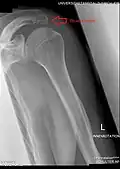

Acromion